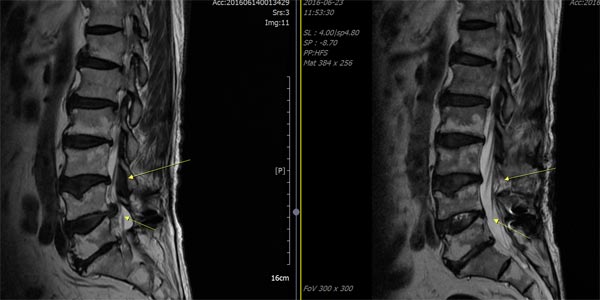

① 허리 디스크(추간판 탈출증)

척추뼈 사이에는 탄력 있는 쿠션 역할을 하는 '추간판'이 있습니다. 이 디스크는 외부의 단단한 섬유륜과 내부의 부드러운 수핵으로 구성되어 있습니다. 나이가 들면서 디스크 내 수분 함량이 감소하면 탄력성이 떨어지게 되고, 무거운 물건을 들거나 갑작스런 움직임이 가해질 때 섬유륜이 파열되어 수핵이 밖으로 튀어나옵니다. 이것이 신경을 압박하면서 심한 허리 통증과 다리 저림 증상이 발생합니다.

② 척추관 협착증

30대 이후부터 척추의 퇴행성 변화가 시작되면서 척추 뼈 사이 공간이 점차 좁아지는 질환입니다. 뼈의 퇴행으로 인해 골극(가시 같은 모양으로 튀어나온 뼈)이 생기고, 주변 인대가 두꺼워져 척추관이 4방향에서 압박됩니다. 결과적으로 척수와 신경근이 눌리면서 다리 저림, 당기는 증상, 장거리 보행 시 통증이 나타납니다.